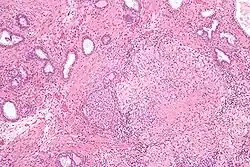

Micrograph showing granulomatous inflammation of bladder neck tissue due to Bacillus Calmette–Guérin used to treat bladder cancer, H&E stain

BCG has been one of the most successful immunotherapies.[35] BCG vaccine has been the "standard of care for patients with bladder cancer (NMIBC)" since 1977.[35][36] By 2014, more than eight different considered biosimilar agents or strains used to treat nonmuscle-invasive bladder cancer.[35][36]

• BCG is used in the treatment of superficial forms of bladder cancer. Since the late 1970s, evidence has become available that the instillation of BCG into the bladder is an effective form of immunotherapy in this disease.[37] While the mechanism is unclear, it appears a local immune reaction is mounted against the tumor. Immunotherapy with BCG prevents recurrence in up to 67% of cases of superficial bladder cancer.